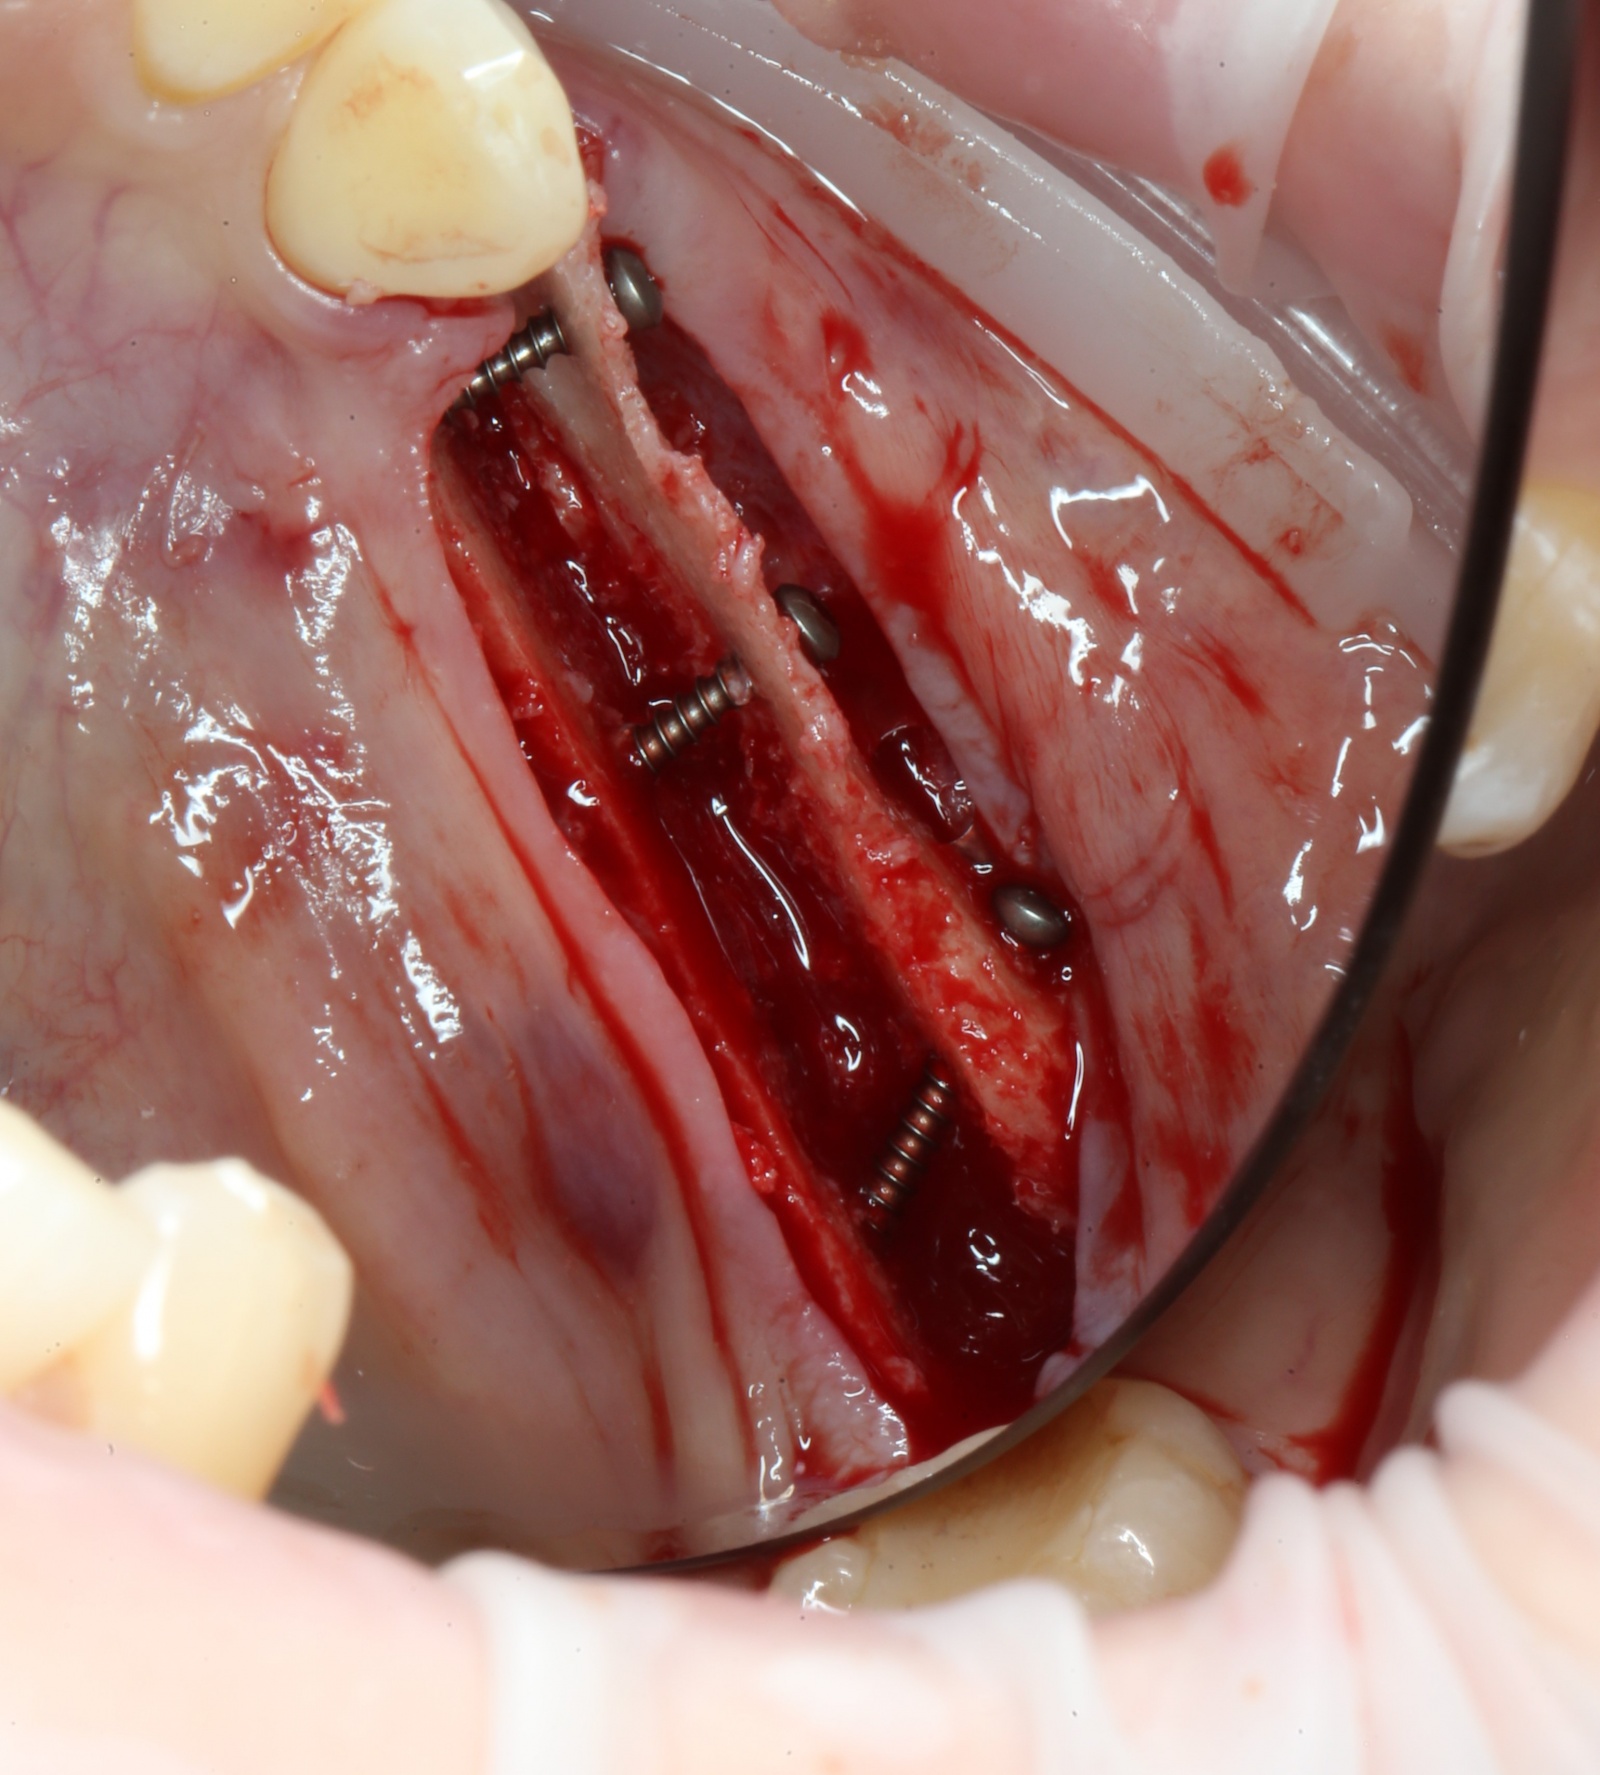

Ультразвуковой наконечник располагается перпендикулярно кости, вследствие чего формируется «траншея» вдоль того участка, где отсутствуют зубы. Глубина этой траншеи составляет 10 мм.

Вид сверху:

При помощи специальных остеотомов

аккуратнейшим образом производится «расклинивание» костных фрагментов. Почему аккуратнейшим? А потому, что костную стенку можно выломать, и вся операция может пойти по бороде.

Кость расщепили:

Для фиксации костного фрагмента, чтобы тот в дальнейшем не отвалился, используются специальные винты.